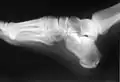

Le calcanéus peut subir des fractures.

Radio d'une fracture du calcanéus.